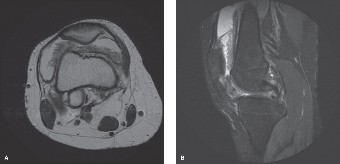

Magnetic Resonance Imaging

Given the chronicity of the symptoms, the boggy effusion, the history of serosanguinous aspirates, and the subtle marginal erosions on plain radiographs, a Magnetic Resonance Imaging (MRI) scan of the left knee was strictly indicated. Standard protocols including T1-weighted, T2-weighted, Proton Density (PD), and Gradient-Recalled Echo (GRE) sequences were obtained, both with and without intravenous Gadolinium contrast. The MRI proved to be the definitive diagnostic modality.

The MRI findings demonstrated diffuse, exuberant, hypertrophic synovitis involving all compartments of the knee joint. The synovial proliferation extended extensively into the suprapatellar pouch, the medial and lateral gutters, the intercondylar notch, and the posterior joint recesses. The synovium exhibited a striking frond-like, villonodular architecture.

The most critical and pathognomonic finding was the presence of extensive areas of low signal intensity on both T1- and T2-weighted sequences within the hypertrophic synovial masses. On the Gradient-Recalled Echo (GRE) sequences, these areas demonstrated a prominent "blooming artifact." This magnetic susceptibility artifact is caused by the paramagnetic properties of extensive hemosiderin deposition within the synovial tissue, a hallmark of Pigmented Villonodular Synovitis (PVNS).

Following the administration of intravenous Gadolinium, the thickened synovial tissue demonstrated avid, heterogeneous enhancement, confirming the highly vascular nature of the proliferative process.

Furthermore, the MRI allowed for precise evaluation of the articular cartilage and subchondral bone. The articular cartilage appeared focally thinned in several areas, particularly over the medial femoral condyle. The MRI clearly delineated the subchondral bone erosions previously suspected on plain radiographs, confirming their presence on the medial femoral condyle and the posterior aspect of the tibial plateau. These erosions were filled with the same low-signal, hemosiderin-laden synovial tissue. Notably, there was no significant surrounding bone marrow edema adjacent to these erosions, a finding that helps differentiate chronic, slow-growing erosions of PVNS from acute inflammatory or infectious erosions.